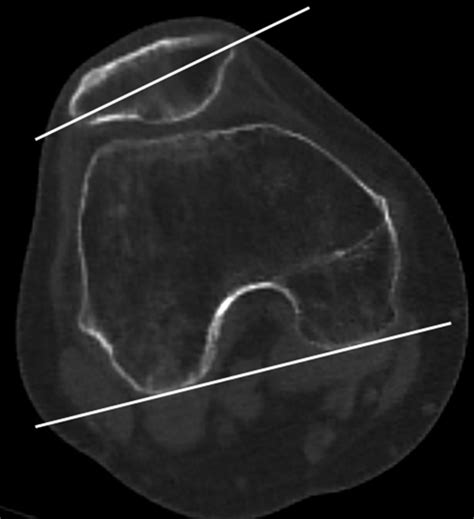

• lateral patellar tilt angle

• lateral patellar tilt radiopaedia